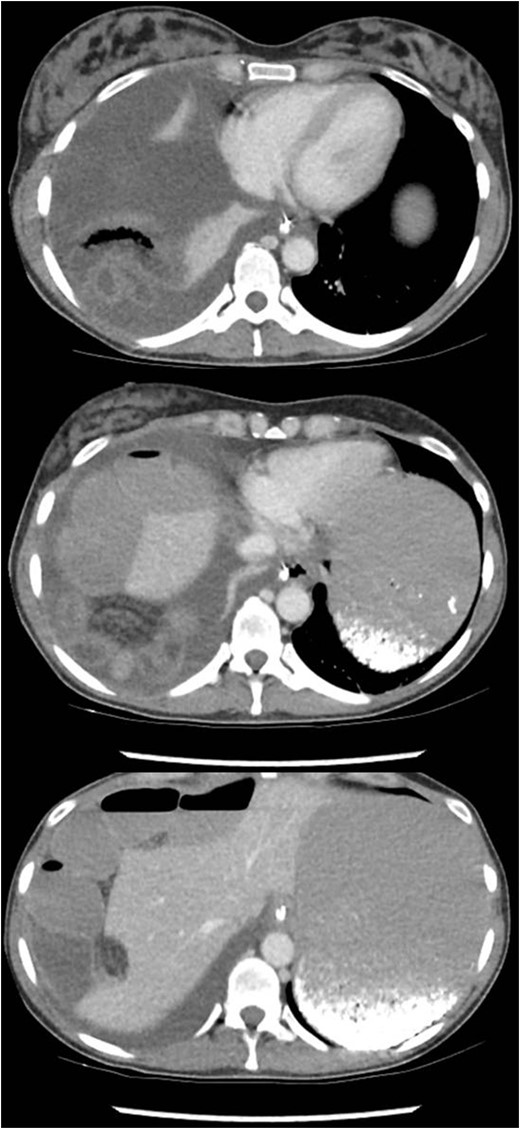

A 10 mm port was inserted infraumbilically using Hasson technique, with an additional three operating ports. Laparoscopy confirmed radiological findings of a right-sided diaphragmatic defect with herniation of terminal ileum.

There was evidence of small bowel obstruction, with distended small bowel loops and constriction at the defect. The defect’s location did not appear consistent with a congenital hernia. The hernia was reduced by gentle traction and the defect was closed laparoscopically with interrupted 0-monosof sutures. The entire small bowel was viable and intact (Fig. 3).

Identification and laparoscopic reduction of diaphragmatic hernia in sequence. Green borders outline small bowel; red borders delineates hepatic edge; yellow margins signifies diaphragmatic defect; and purple hashed line is closed defect.